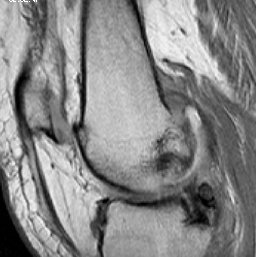

In this case arrows to highlight the abnormality are displayed only on user's request after the user clicks on description or diagnosis.

Case 4

5976.jpg (16246 bytes)6040.jpg (13715 bytes)

History

Description

Diagnosis